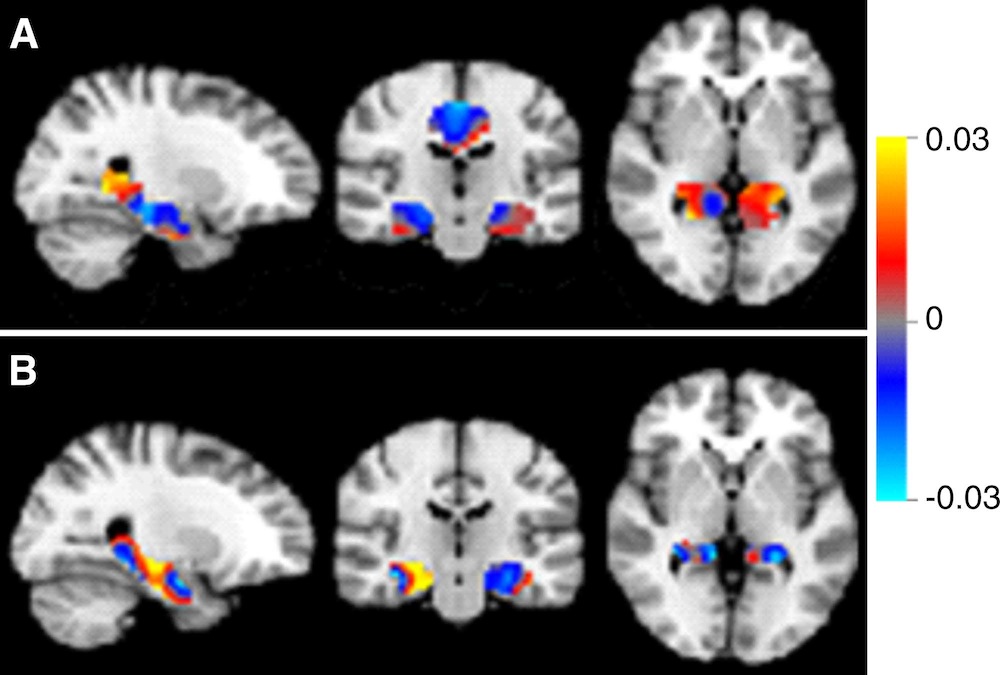

Discrimination maps for classifying mild cognitive impairment (MCI) subgroups, inside the masks that resulted in the highest accuracies. A: between patients with MCI that converted to Alzheimer’s disease (MCIc) and subjects with subjective cognitive decline (SCD); B: between MCIc and patients with MCI that remained stable (MCIs).

In these brain scans, the classifiers can be represented as discrimination maps, where a red color indicates that the intensity at that location contributes to the likelihood of the images belonging to the more advanced stage, and a blue color to the likelihood of belonging to the less advanced stage.